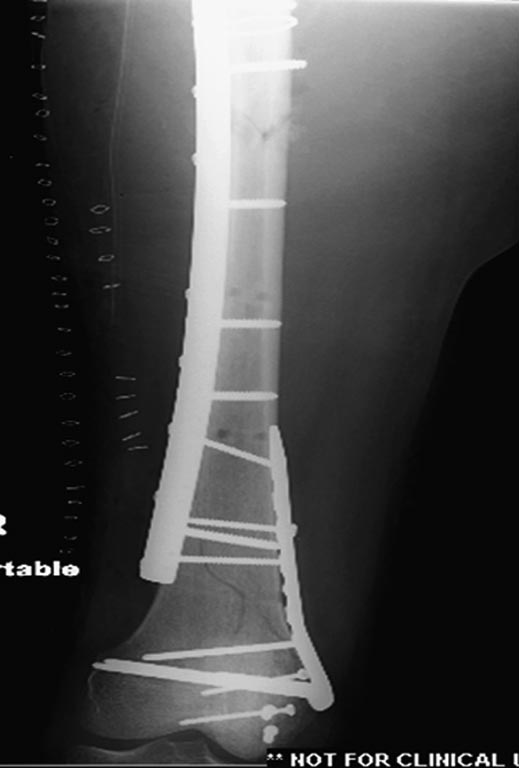

Интрамедуллярный остеосинтез бедра PFN Long

Интрамедуллярный остеосинтез плеча лучше в одну операцию при стабильном общем состоянии

При подборе фиксатора необходимо ориентироваться на следующие моменты: максимальный бенефит при минимальной инвазивности, создание стабильности при многоуровневом переломе, и наличие опыта работы с имплантатом. А предложенный фиксатор (PFN Long) не отвечает требованиям, потому что фиксатор предназначен для чрез-под вертельных и для высоких переломов бедра. Сомнения по поводу толстого (11 мм) болта в головку, хотя более пожилым с агрессивными конструкциями в головку проблем не бывает, а для молодых без надобности большие конструкции не рекомендуются. Лучше менее агрессивные, например, тонкие параллельные или перекрестные винты в проксимальном отделе гвоздя.

При лечении ипислатеральных переломов шейки и бедра лучший биомеханический эффект обеспечивают независимые друг от друга имплантаты, например, винты или DHS, и отдельная фиксация диафиза бедра. Можно интрамедуллярную фиксацию, но тогда, закрывая диафиз, мы отрезаем возможности фиксировать перелома шейки и головки!

Раны в области коленного сустава и на плече до сих пор чистые, остаются открытыми. Отсутствует признаки инфекции, решили превратить недостаток в преимущество, т.е. фиксировать через открытые раны пластинами.

На 9й день фиксация дистального бедра, где фрагмент Hoffa и вертикальный перелом надколенника, зафиксированы винтами.